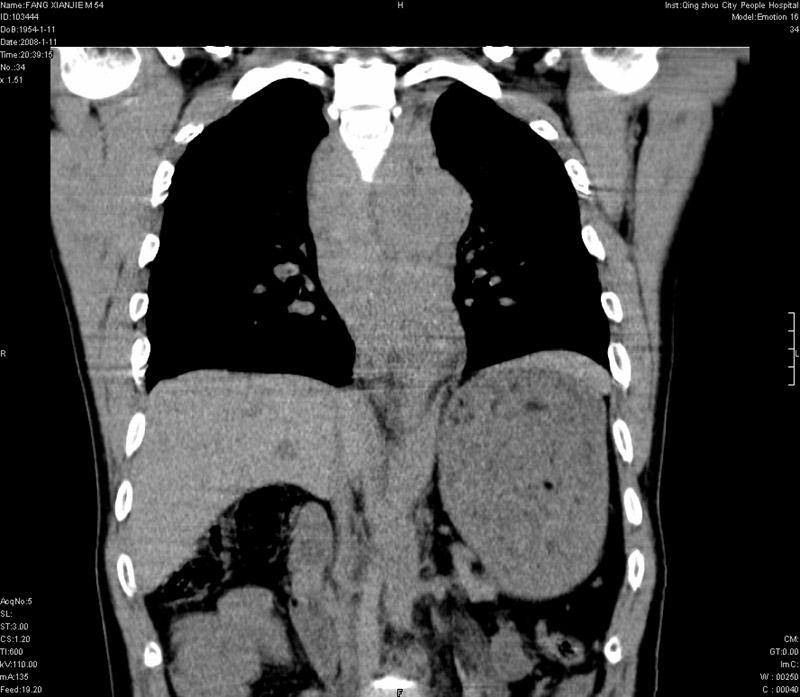

男性,40岁。胸部被车压伤伴胸痛1小时来院就诊。检查:一般情况尚可,血压110/80,胸部及上腹部压痛。结果在三天后公布。骨窗在横断位、冠矢状显示肋骨、胸椎、和胸骨未见骨折征象。

ct11308:胸部外伤1小时(证实病例) (2008-1-13 16:2)结果如下:病人入院后两小时后症状加重,8小时后在征得病人家属同意做了ct增强扫描。如下图。最终临床诊断:外伤性胸主动脉破裂并纵隔内血肿。由于有运动性伪影,胸骨在矢状面重建的图像似有骨折征,这是一种假象,我们称之为“假骨折”,这在多层ct重建中经常性遇到,必要时要结合横断图像鉴别之。现在,病人的一般情况较差,是否要手术家属尚有争议,如果手术修补,难度较大,需要专门预定制作固定支架。

当然,对于该病例,其它非重要的诊断还有:右侧少量气胸;左侧胸腔积液;左侧轻度肺挫裂伤。对于纵隔内血肿,我们曾经遇到过多例,也有怀疑主动脉的破裂,但是,均未得到具体出血部位的明确诊断。